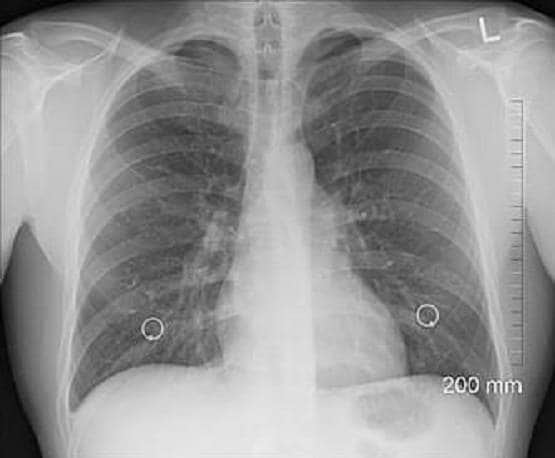

यूनिवर्सिटी ऑफ डेटॉन रिसर्च इंस्टिट्यूट के एक वैज्ञानिक बराथ नारायणन का कहना है कि उनका यह सॉफ्टवेयर  कोड इंसान की चेस्ट को स्कैन कर शरीर में छिपे वायरस का पता लगा सकता है.

Picture: University of Dayton Research Institute

इतना ही नहीं, नारायणन का यह भी कहना है कि शरीर में छिपे वायरस के बारे में यह सॉफ्टवेयर 98 प्रतिशत तक सही चीजें बताने में सक्षम है. उन्होंने डेली मेल को एक ई-मेल कर इसका दावा किया है.

नारायणन का कहना है कि यह विशेष सॉफ्टवेयरस सामान्य एक्स-रे स्कैनिंग मशीन से एकदम अलग है. इसे आर्टिफिशियल इंटेलिजेंस (एआई) तकनीक से जोड़ा गया है जिसका रिजल्ट 98 से 99 प्रतिशत तक सही हो सकता है.